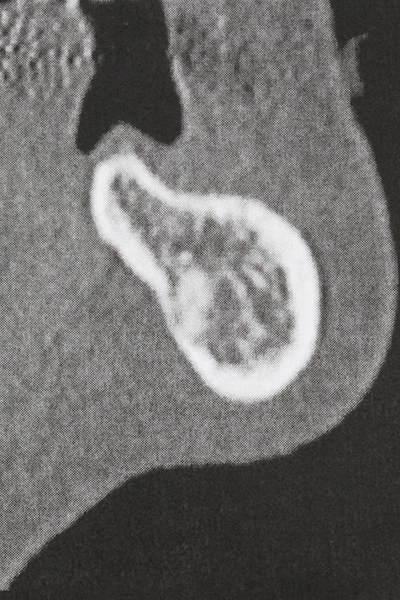

Si es preciso realizar intervenciones quirúrgicas en las que el hueso está en contacto directo con estructuras sensibles, como son los vasos sanguíneos o los nervios, los instrumentos rotativos presentan un enorme potencial de provocar lesiones iatrogénicas. Así, precisamente en la representación de nervios después de una lesión iatrogénica, o en el transcurso de la lateralización de un nervio para resecciones, reconstrucciones o incorporación de implantes, los equipos piezoeléctricos pueden resultar muy útiles para preparar la tapa ósea y retirar las partes de tejido duro cercanas al nervio (fig. 17-20). Por lo general, un ligero contacto del cordón nervioso con el inserto piezoeléctrico no tiene consecuencia alguna; ahora bien, un procedimiento poco cuidadoso con movimientos tipo sierra o piezas de trabajo sobre la base ósea aún existente puede provocar lesiones nerviosas temporales o incluso permanentes. Con todo, el riesgo de sufrir una lesión de este tipo se considera significativamente inferior que en los casos en los que se utilizan sierras y fresas (Pereira, Gealh et al. 2014).